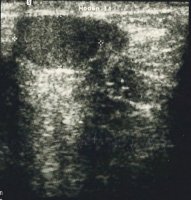

Wie im Beispiel eines 15 Jahre alten Jungen mit palpablen, normothopen, kleinen Hoden links.

Das rechte Hodenfach war palpatorisch leer, am äußeren Leistenring war fragliches Hodengewebe tastbar ("Hodenknospe"). In der Sonographie zeigte sich ein rudimentäres Hodengebilde (Abbildung 9a).

Die Freilegung ergab einen kleinen, geschrumpften rechtsseitigen Hoden (Abbildung 9b).